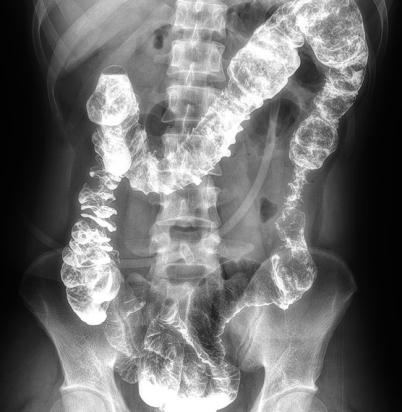

多功能動(dòng)態(tài)平板DR,采用U型臂結(jié)構(gòu),具有靜態(tài)DR攝影、數(shù)字透視、數(shù)字造影和可視化攝影的功能。

● 可快速選擇、預(yù)設(shè)所需要的視野,節(jié)約擺位時(shí)間;

● 根據(jù)拍攝需求或技師使用習(xí)慣一鍵切換光束范圍;

● 可根據(jù)不同的體位協(xié)議,自動(dòng)調(diào)整光束大小。